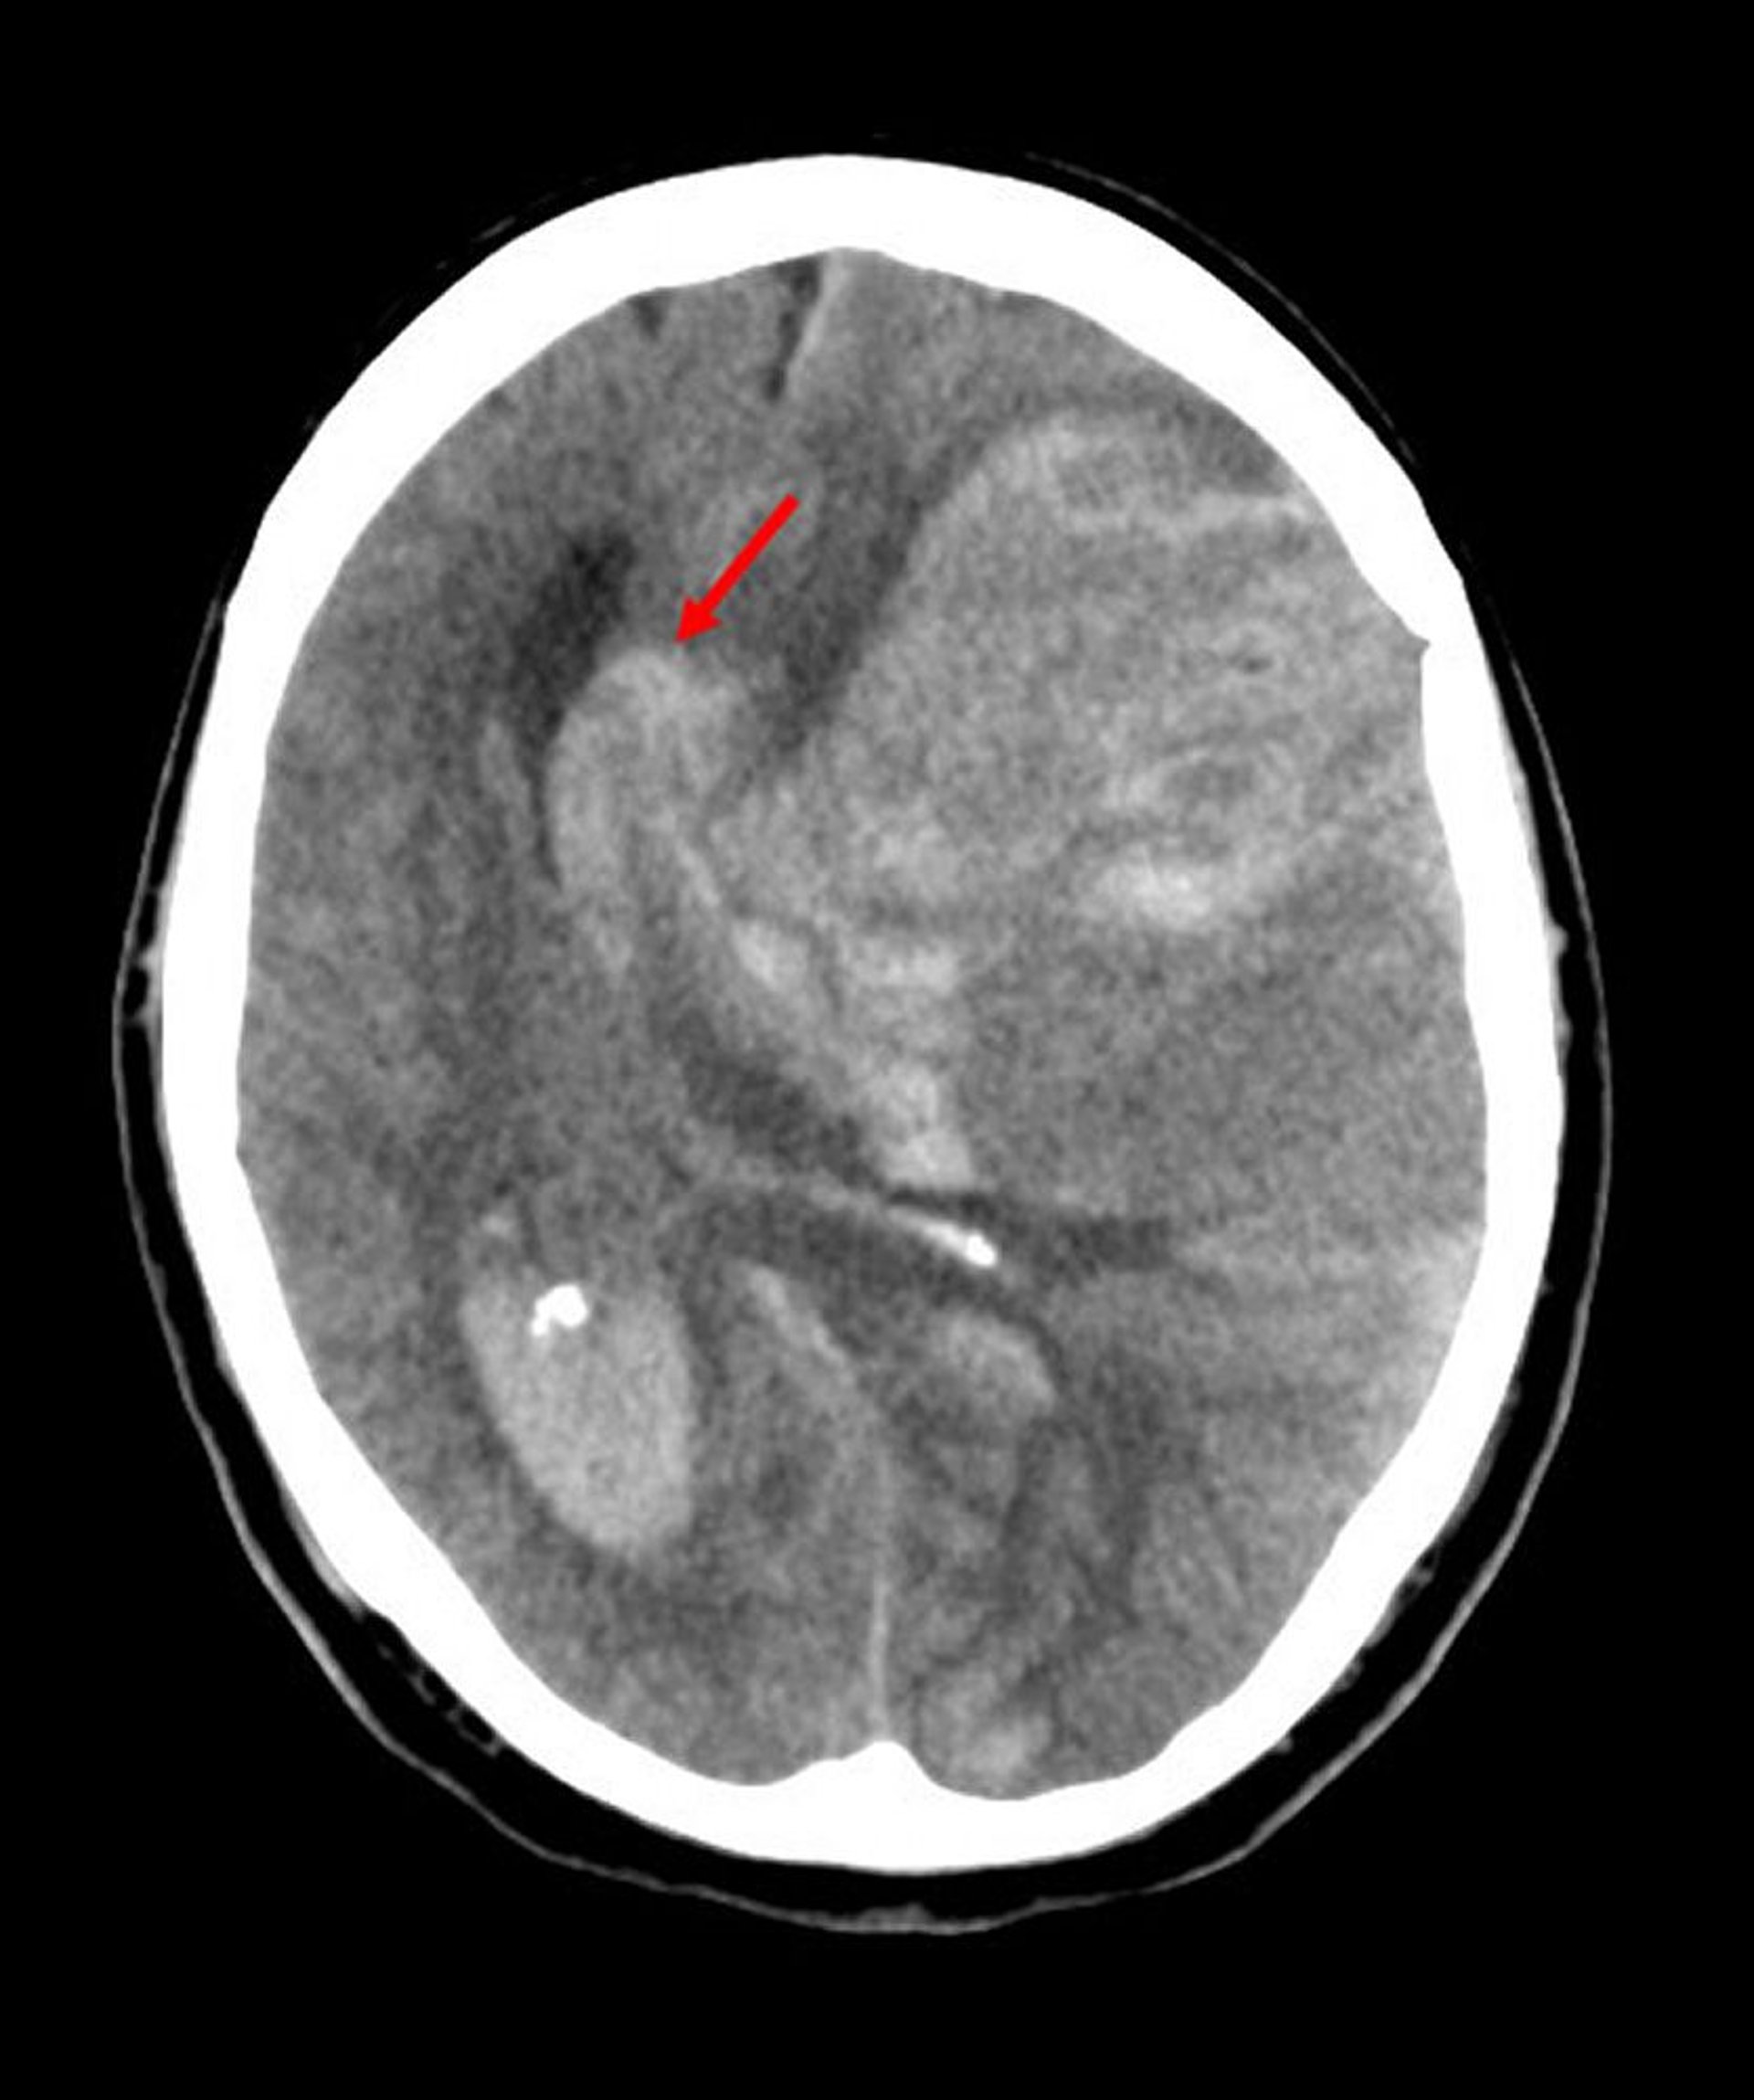

Hérnia subfalcina é o tipo mais comum de hérnia cerebral. Nessa imagem, o hemisfério esquerdo herniou pela borda livre da foice cerebral (seta) devido ao sangramento de um infarto na artéria cerebral média que aumentou a pressão intracraniana.